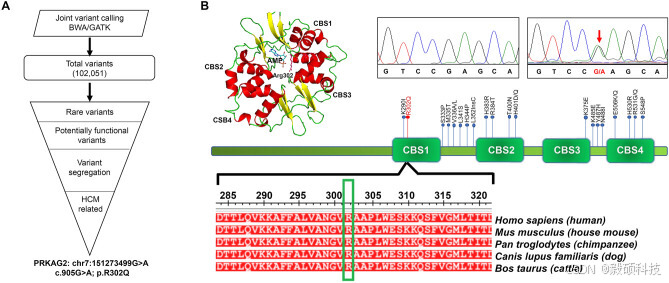

为了对 PRKAG2 心肌病患者进行深度表型,研究组对三个家族的 8 名受试者进行心脏磁共振成像(CMR)检查。研究显示,重症患者存在弥漫性严重同心左心室肥厚和右心室肥大。为了了解 3 个家族中观察到的肥厚型心肌病表型的因果变异,对43 人进行全外显子组测序。并进行联合变异调用,结果发现了 102 051 个核苷酸变异。

研究组只筛选了罕见变异(MAF < 0.1%),然后确定了预测会对蛋白质功能产生影响和/或与疾病相关的罕见变异。在疾病遗传模式进行叠加后,筛选出了通过受影响和未受影响的家庭成员进行遗传的致病变异。发现了一个致病性常染色体p.Arg302Gln突变,该突变影响了 AMP/ ATP 结合口袋。通过对所有个体进行 Sanger 测序,验证了PRKAG2 突变。该突变在所有三个家族中都显示出完全的表型基因型相关性。因此研究组进行了无偏的亲缘关系分析,以检查所有家系是否来自同一创始群体。在对亲缘关系矩阵的分层聚类分析中,这三个家系之间没有任何亲缘关系,并形成了三个不同的聚类。

图6 研究队列中三个家族中偶然变异的鉴定